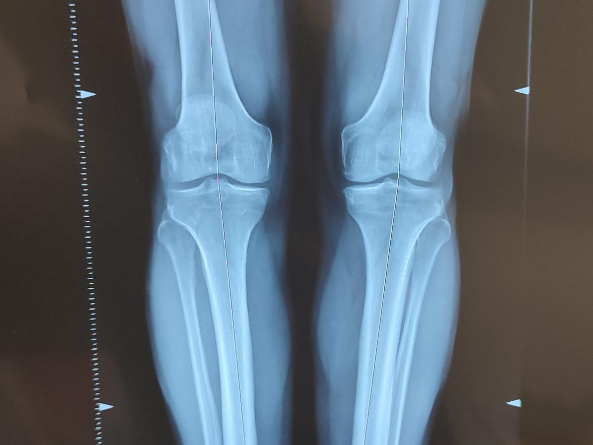

Quand l’axe du membre est déformé, les contraintes mécaniques sont mal réparties entre les deux compartiments fémoro-tibiaux, ce qui accélère l’usure cartilagineuse. Lorsque cette dernière n’est pas trop importante, il est possible de freiner son évolution en corrigeant l’axe du membre inférieur par une ostéotomie.

La planification préopératoire de cette intervention est essentielle car la principale cause d’échec est la non-correction ou l’hyper-correction de la déformation initiale. Il faut aussi repérer l’origine de cette déformation (tibiale ou fémorale) pour guider le geste chirurgical.

En complément de l’analyse radiographique, de grandes avancées technologiques ont émergé ces dernières années pour permettre de planifier sereinement cette chirurgie (Navigation assistée par ordinateur, guides de coupe imprimés par des imprimantes 3D).